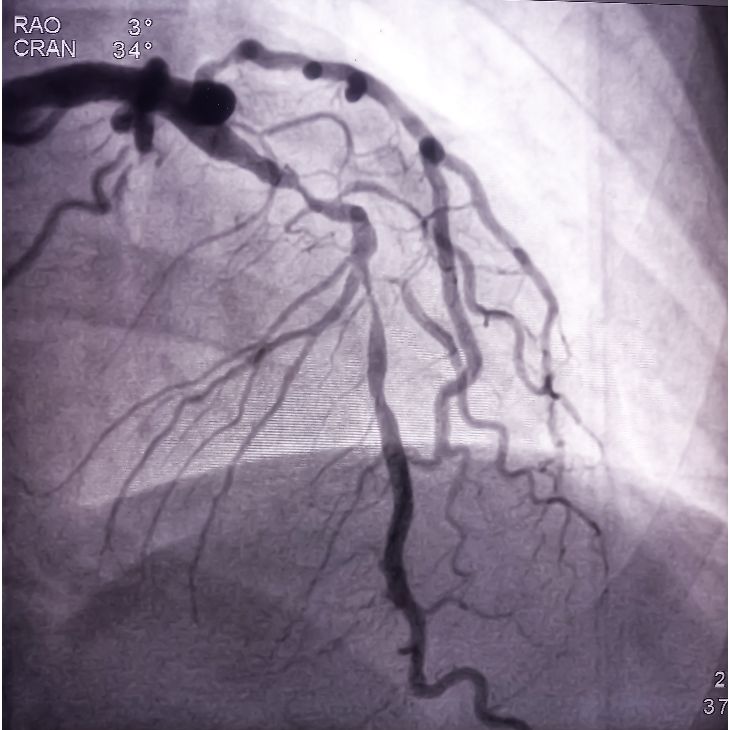

Coronary angiography is a gold-standard test used to visualise the heart’s arteries and detect blockages or narrowing. As a leading consultant cardiologist and internationally recognised expert in coronary physiology, I use advanced techniques to deliver accurate, minimally invasive diagnosis.

During the procedure, a thin catheter is inserted into the wrist or groin and guided to the heart. Contrast dye is injected, and X-ray images reveal the condition of the coronary arteries. This procedure helps determine the best treatment – such as stenting or bypass surgery. Performed under local anaesthetic, most patients return home the same day.